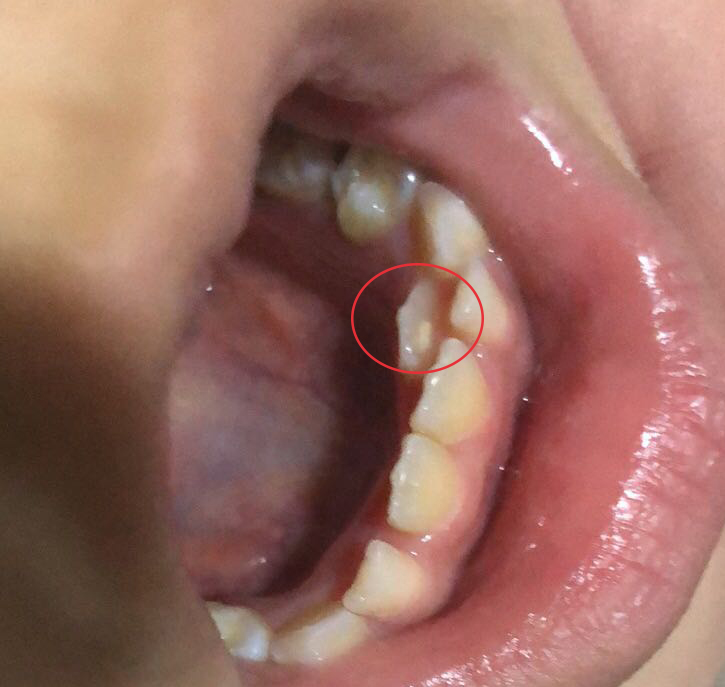

每个人通常都会长两幅牙,首先萌出的是乳牙,等到6岁左右进入替牙期,乳牙逐渐脱落,伴随一生的恒牙随之萌出。乳牙除了维持幼儿期咀嚼、发音等功能,还有着引导恒牙萌出的作用。如今,有很多孩子由于饮食过于精细,乳牙迟迟不脱落,导致恒牙错位萌出,形成双排牙。

这时候医生通常会建议将孩子滞留的乳牙拔除。家长们就很担心,乳牙拔掉后,已经错位萌出的恒牙还会自动归位吗?汕头口腔医疗中心儿童齿科医生表示,滞留乳牙拔除后,错位恒牙是否能归位,主要受错位恒牙的位置及乳牙拔除时机影响。

一般情况下,拔牙后,恒牙会朝着正常位置生长,若恒牙错位的程度比较轻微,就在乳牙附近,那么自行归位的可能性较大,相反,恒牙错位比较严重,萌出位置较远或有扭转,那么归位的可能性较小。

另一方面,如果滞留乳牙能够及时拔除,恒牙复位的时间就比较充足,若是恒牙已经萌出大部分或完全萌出,没有足够时间回到正常位置,可能出现无法归位的情况,需要在换牙后考虑牙齿正畸。因此,孩子牙齿出现异常时,妈妈一定要带孩子及时就诊处理。